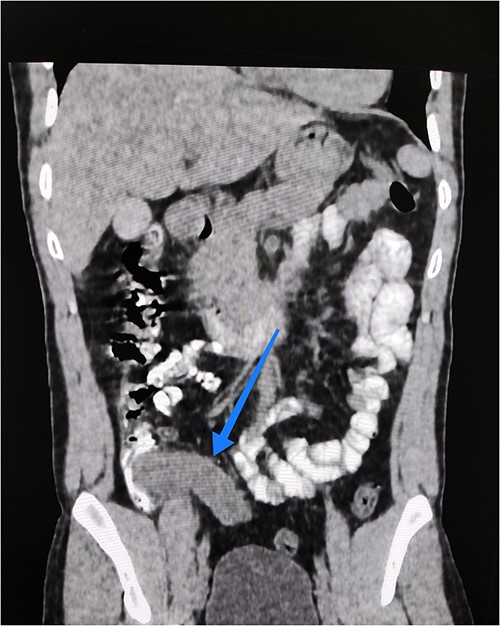

Abdominal ultrasound reported a mass with a cystic component at the right iliac fossa with unclear margins, suggestive of an appendicular abscess. Consequently, a computed tomography (CT) abdomen with oral and IV contrast was requested. It showed an oblong, fluid-filled structure originating from the medial side of the caecum, 14 cm long and 3 cm wide, with a wall thickness of 5.3 mm, extending down to the pelvis (Fig. 1). This resulted in a provisional diagnosis of either an appendiceal mucocele or mucinous appendiceal neoplasm.

Coronal view of abdominal contrast CT showing the oblong structure originating from the medial side of the caecum and extending down to the pelvis.